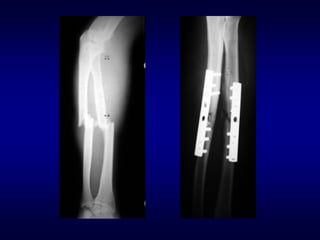

Treating the fracture

• How are we going to hold the reduction?

– Semi-rigid (Plaster)

– Rigid (Internal fixation)

Indications for operative treatment

• General trend toward operative treatment last

30 yrs

– Improved implants and antibiotic prophylaxis, use

of closed and minimally invasive methods

• Current absolute indications:

– Polytrauma, displaced intra-articular fractures

– Open #’s, #’s with vascular injury or compartment

syndrome

– Pathological #’s, Non-unions